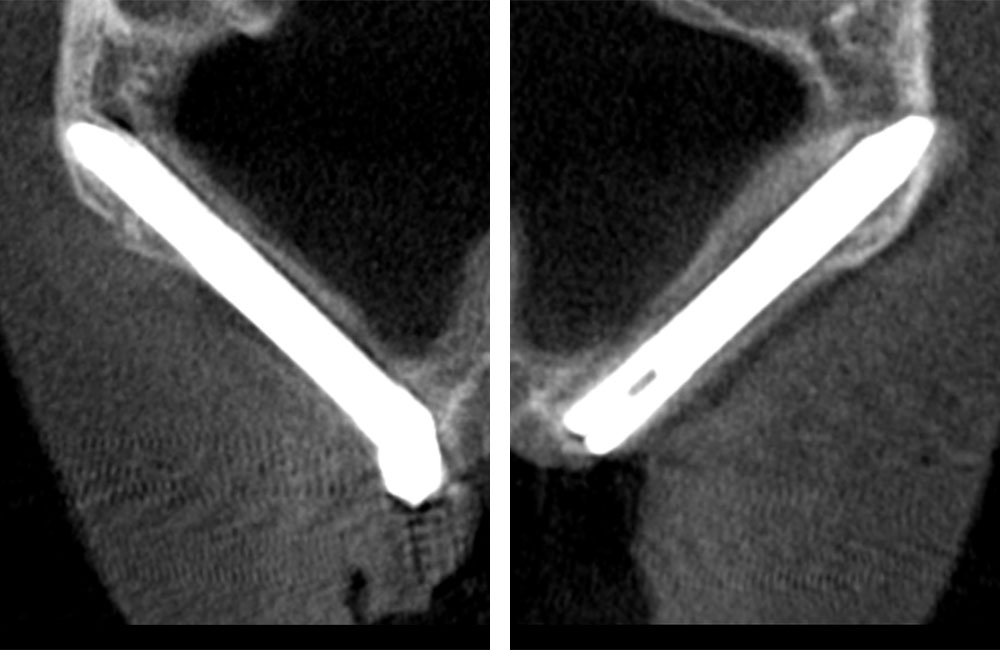

術前のCT画像

左右のザイゴマインプラントが頬骨から大きく飛び出し頬を触ると違和感がある -

術後のCT画像

前方のインプラントは残し、他院埋入のザイゴマインプラントを除去し、同時に新しいザイゴマインプラントを適切な位置に再埋入を行っております。治療後数年経過しておりますが良好な状態を保っております。